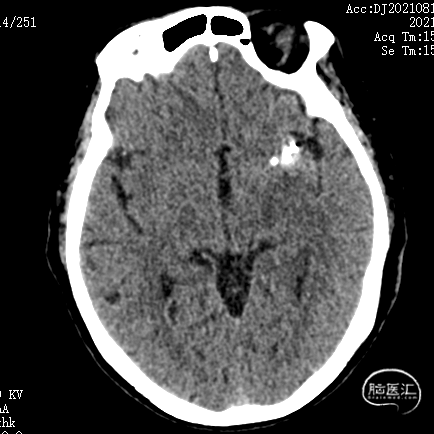

术后3天复查CT示:

1. 双侧基底节区腔隙性脑梗死;

2. 老年性脑改变;

3. 左侧颞叶致密影,考虑术后,请结合临床病史。未见大脑前载瘤动脉远端存在缺血。

术后6个月复查造影示:弹簧圈致密充填瘤体内,瘤体消失,左侧颈内动脉及大脑前、中动脉均显影良好,载瘤动脉通畅,形态和血管直径较动脉瘤栓塞前无明确变化。支架形态良好,未见移位及血栓形成。